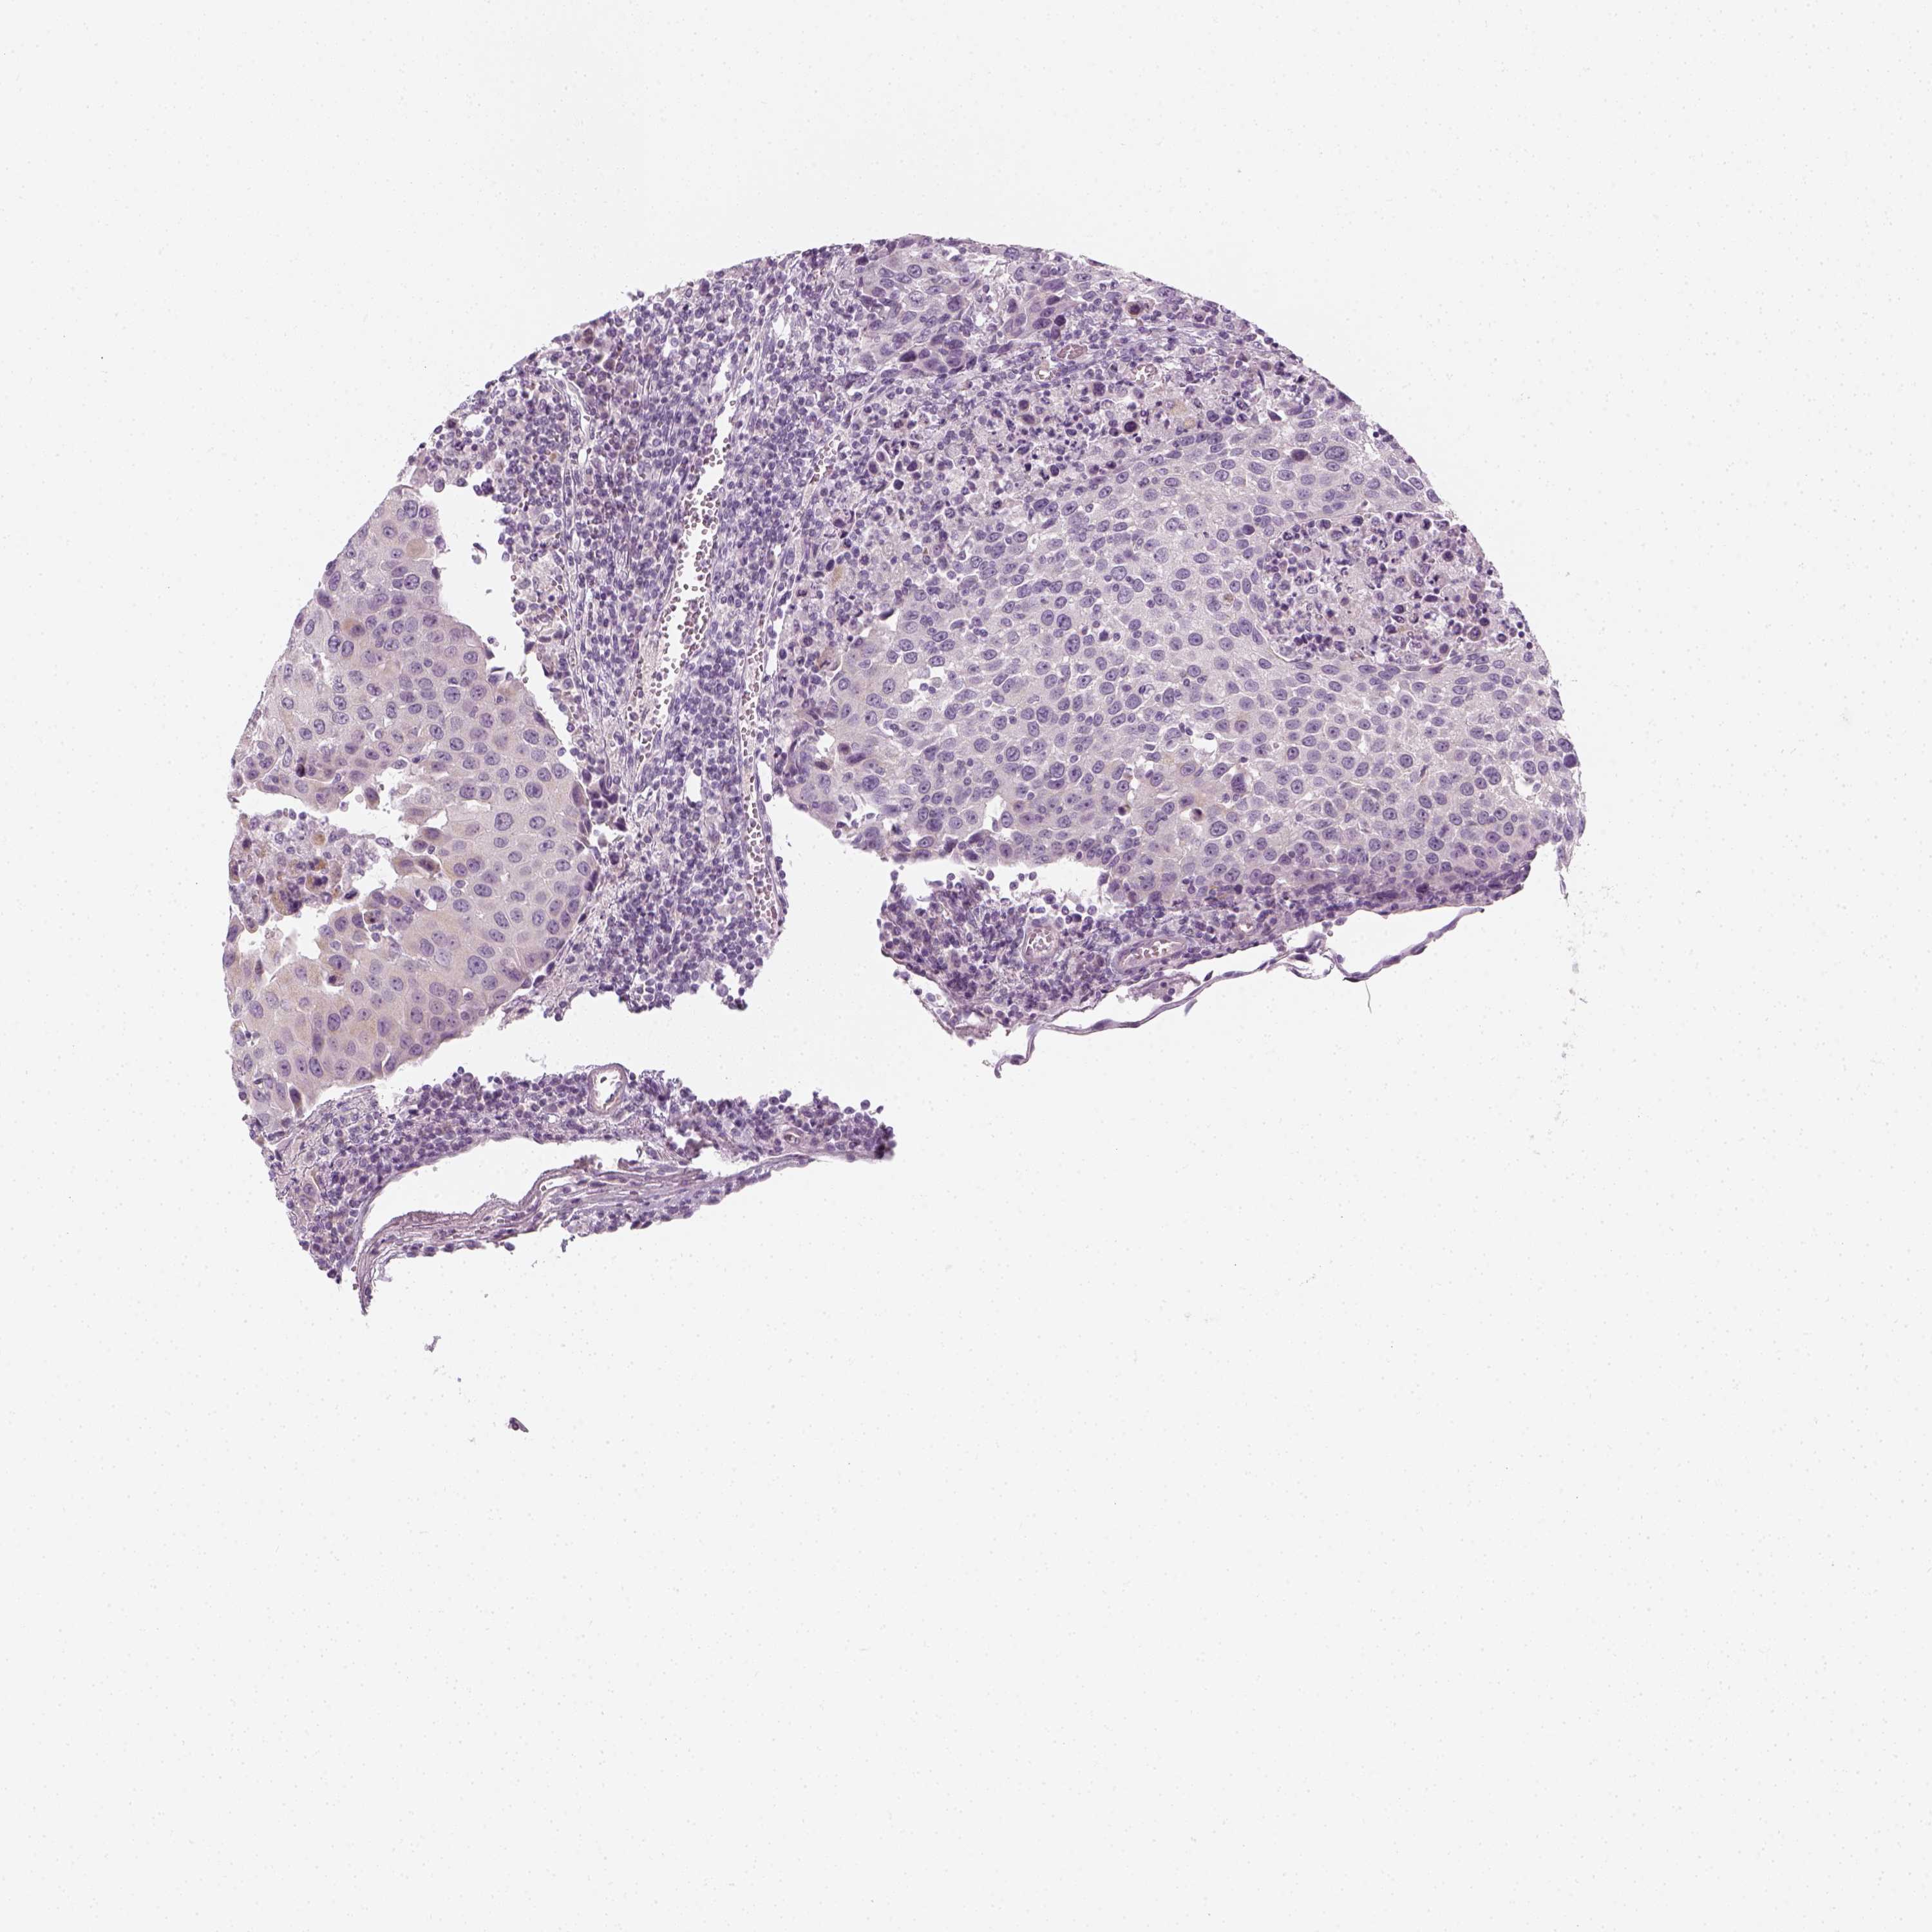

UROTHELIAL CANCER - Protein expressioni

A mouse-over function shows sample information and annotation data. Click on an image to view it in a full screen mode. Samples can be filtered based on level of antibody staining by selecting one or several of the following categories: high, medium, low and not detected. The assay and annotation is described here.

Antibody stainingi

Antibody staining in the annotated cell types in the current human tissue is reported as not detected, low, medium, or high, based on conventional immunohistochemistry profiling in selected tissues. This score is based on the combination of the staining intensity and fraction of stained cells.

Each image is clickable and will lead to virtual microscopy that enables deeper exploration of all samples and also displays staining intensity scores, fraction scores and subcellular localization as well as patient and tissue information for each sample.

Antibody HPA045153

Antibody CAB080138

Staining

High

Medium

Low

Not detected

Intensity

Strong

Moderate

Weak

Negative

Quantity

>75%

75%-25%

<25%

None

Location

Nuclear

Cytoplasmic/membranous

Cytoplasmic/membranous,nuclear

Urothelial carcinoma, High grade

Urothelial carcinoma, NOS

Urothelial carcinoma, Low grade